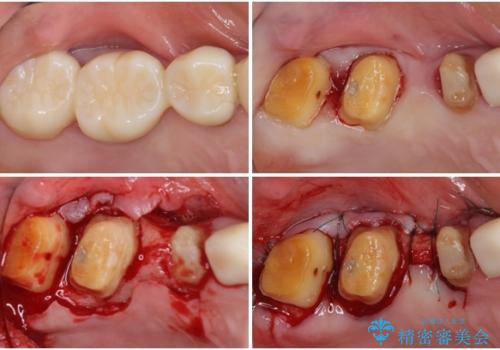

奥歯の歯槽骨が失われた 歯周外科処置後のセラミックブリッジ

- 歯磨きの度に奥歯から出血があることを気にして来院された患者様です。

咬み合わせにより発現した歯周ポケットに汚れがたまり、歯周病のような状態になってしまっていました。

失われていた歯槽骨を、再生治療により可及的に改善させ、その1年後に歯周ポケットを除去するための歯周外科処置を行うこととしました。

処置後はオールセラミックブリッジにて補綴し、再発防止のために就寝時にナイトガード(マウスピース)を装着していただくこととしました。